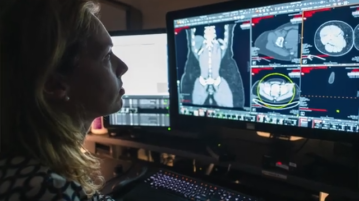

Pancreatic Cancer Predictor: AI Early Warning System

BOSTON, Mass. (Ivanhoe Newswire) — Each year in the U.S., more than 66,000 people are diagnosed with pancreatic cancer. 51,000…More